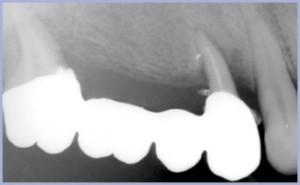

La paziente è affetta da diabete lieve in compenso, portatrice di parodontopatia cronica con riassorbimento osseo prevalentemente orizzontale, in terapia di mantenimento. Presenta una perdita di supporto dentale con diastema centrale (fig. 33) e triangoli neri interdentali. Il labbro nasconde la zona gengivale. Presenta inoltre edentulia intercalata al 3° quadrante (Kennedy VI) e, di fatto, una edentulia distale bilaterale superiore (Kennedy I), essendo la protesi al I° quadrante non recuperabile (figg. 1-4).

Il piano di trattamento prevede la rimozione della protesi sui pilastri 7+ 3+ non recuperabili e la riabilitazione implanto-protesica al 1° e 3° quadrante mediante utilizzazione di impianti “Exacone®” a connessione conometrico-esagonale. Si inseriscono 3 fixture in sede 4+ (post-estrattivo immediato) 5+ e 6+ in tecnica bifase (figg. 5-12). La fase di laboratorio prevede il fresaggio dei tre monconi e la realizzazione della travata metallica sui tre elementi (figg. 13-14). Al momento della prova in bocca dei monconi fresati e della travata (figg. 15-18), si esegue estrazione di 7+ (figg. 19-20). Dopo la consegna del lavoro ultimato, si attivano i tre monconi negli impianti e si cementa sopra la protesi (figg. 21-27).